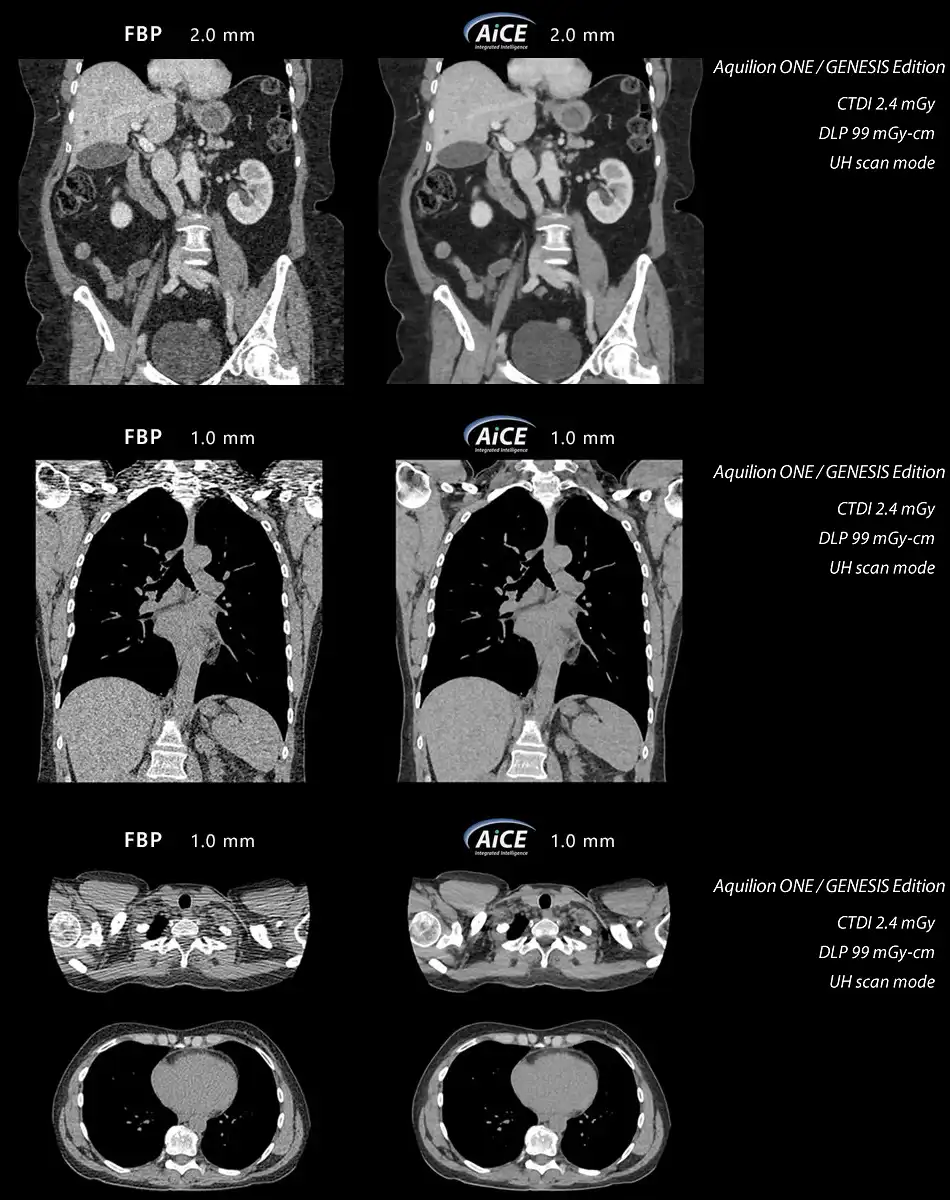

AiCE is a revolutionary approach to CT reconstruction that leverages Deep Learning Neural Networks specifically trained to perform one task – reconstruct images that are sharp, clear, and distinct.

Body, Lung and Cardiac